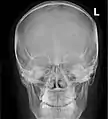

![]() مخطط أمامي للجيوب الجانبية الأنفية | |